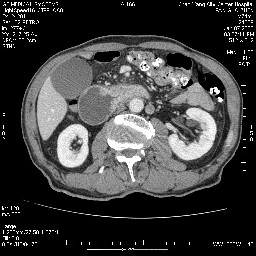

女,74岁,呕吐10余日

壶腹部的占位性病变,考虑为十二指肠癌并梗阻,但脾内多发性低密度区为转移吗?

还有胃、脾之间可见有侧支循环建立。左肾盂积水。

考虑来源于十二指肠水平段的恶性占位,侵及周围组织,特别是胰腺,可见区域淋巴结肿大,左侧下腔静脉畸形。

十二指肠水平段腔内占位伴梗阻,中等度较为均匀的强化,洗脱慢,区域淋巴结显示增多,符合腺癌表现。下腔静脉变异。

十二指肠降段扩张,水平段狭窄成鼠尾状,肠壁明显增厚,胰腺勾突增大成不均匀强化,其内可见低密度区,胆囊增大,1十二指肠水平段腺癌侵犯胰腺勾突可能大,2胰腺癌侵犯十二指肠(只有胆囊增大没有肝内外胆管扩张不好解释)代除外.

十二指肠降段扩张,水平段狭窄成鼠尾状,肠壁明显增厚,胰腺勾突增大成不均匀强化,其内可见低密度区,胆囊增大,1十二指肠水平段腺癌侵犯胰腺勾突可能大,2胰腺癌侵犯十二指肠 。

今日手术结果:胰腺钩突癌侵犯十二直肠,腹腔淋巴结转移.